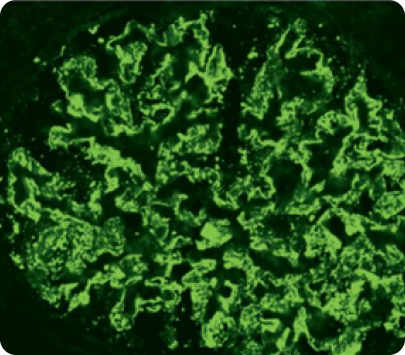

ИФА6

Image

ИФА

• Позволяет определить иммунологическую структуру депозитов. Преобладание свечения одного из иммунных компонентов депозитов более чем на два порядка свидетельствует о диагностически значимой роли данного компонента.